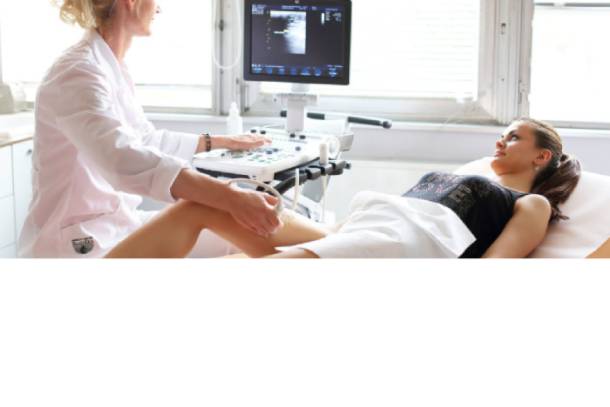

УЗИ ЩИТОВИДНОЙ ЖЕЛЕЗЫ - НАДО ПРОВЕРЯТЬ ИЛИ "РАЗВОД" НА ДЕНЬГИ?

Щитовидная железа является железой производящей важные для организма гормоны. Сложная экология, пища, содержащая канцерогены, а главное, недостаток йода в нашем питании и воде, приводят к различным заболеваниям щитовидной железы у детей и взрослых.